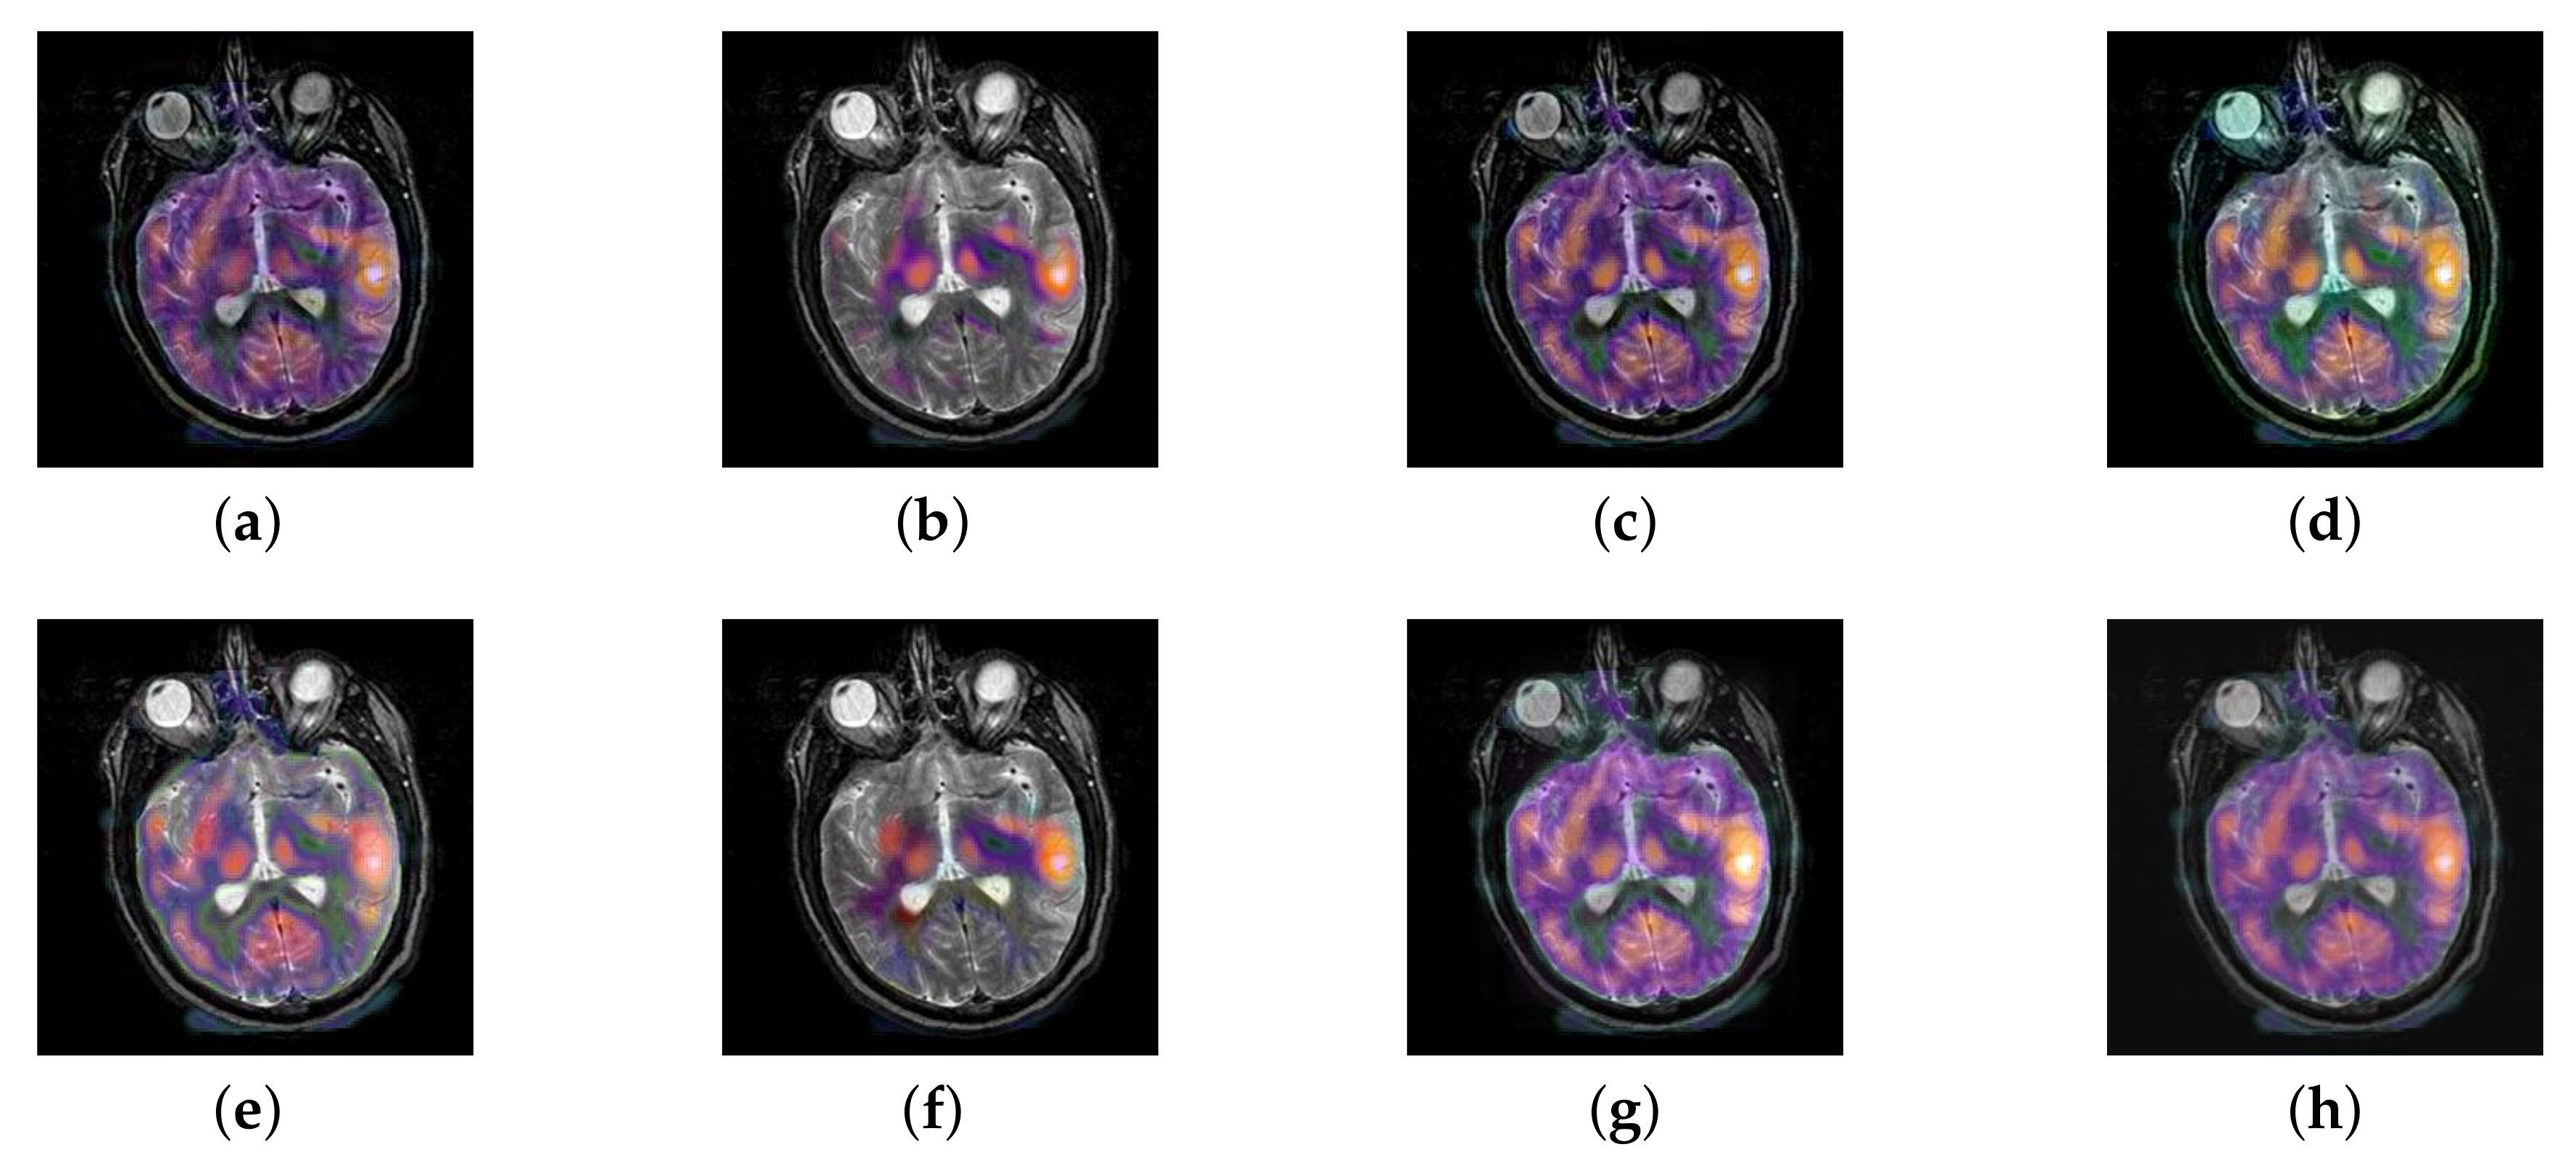

In this section, all FDG images are derived from the normal human brain, but the angle is chosen differently in Figure 24. In Figure 25, Figure 26, Figure 27 and Figure 28, we find that the color information obtained by the image fusion method based on NSCT, DTCWT, and LPSR is better preserved, but the structure information is lost more. The fusion image based on GFF, IGM, and FusionCNN method retains the complete structure information in the MRI image, but the color obtained from the FDG image is distorted. The image color information obtained by DDcGAN fusion method is too bright, resulting in unclear color area details and low contrast of color region. In contrast, the image obtained by our algorithm has moderate brightness of color information, complete structure information, and complete biological detail information.

Figure 25.

Fused medical images obtained by different algorithms (Figure 24a,b): (a) DTCWT, (b) GFF, (c) NSCT, (d) LPSR, (e) IGM, (f) FusionCNN, (g) DDcGAN, and (h) FusionNet.

Figure 26.

Fused medical images obtained by different algorithms (Figure 24c,d): (a) DTCWT, (b) GFF, (c) NSCT, (d) LPSR, (e) IGM, (f) FusionCNN, (g) DDcGAN, and (h) FusionNet.

Figure 27.

Fused medical images obtained by different algorithms (Figure 24e,f): (a) DTCWT, (b) GFF, (c) NSCT, (d) LPSR, (e) IGM, (f) FusionCNN, (g) DDcGAN, and (h) FusionNet.

Figure 28.

Fused medical images obtained by different algorithms (Figure 24g,h): (a) DTCWT, (b) GFF, (c) NSCT, (d) LPSR, (e) IGM, (f) FusionCNN, (g) DDcGAN, and (h) FusionNet.